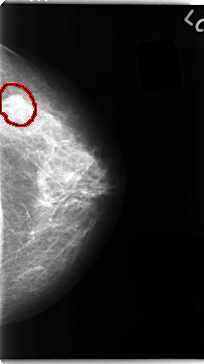

C_0097_1.LEFT_MLO

LEFT_MLO LINES 4672 PIXELS_PER_LINE 2616 BITS_PER_PIXEL 12 RESOLUTION 50 OVERLAY

FILE: C_0097_1.LEFT_MLO.OVERLAY

TOTAL_ABNORMALITIES 1

ABNORMALITY 1

LESION_TYPE MASS SHAPE IRREGULAR MARGINS SPICULATED

ASSESSMENT 5

SUBTLETY 5

PATHOLOGY MALIGNANT

TOTAL_OUTLINES 1

BOUNDARY